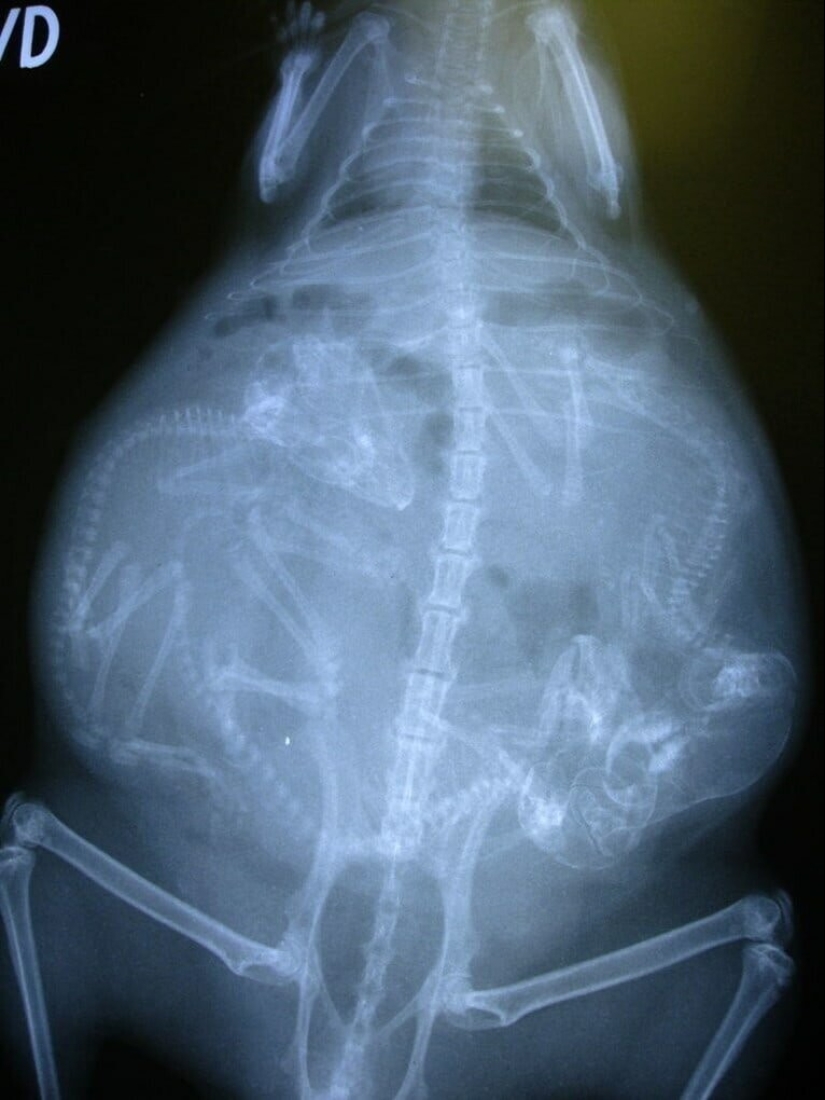

Quién vive en la casita: radiografías de animales preñados

Por Pictolic https://pictolic.com/es/article/quien-vive-en-la-casita-radiografas-de-animales-prenados.html¿Alguna vez te has preguntado qué sucede en el útero de una gata o una perra preñada? ¿Cómo encajan todos estos pequeños bebés allí y logran desarrollarse durante todo el embarazo? La mayoría de los animales preñados se examinan mediante rayos X. Y éstas, cabe señalar, son fotografías muy interesantes.

Especialistas que como parte de su trabajo observan animales que están listos para parir, compartieron estas sorprendentes imágenes de rayos X y ultrasonido.

perra preñada